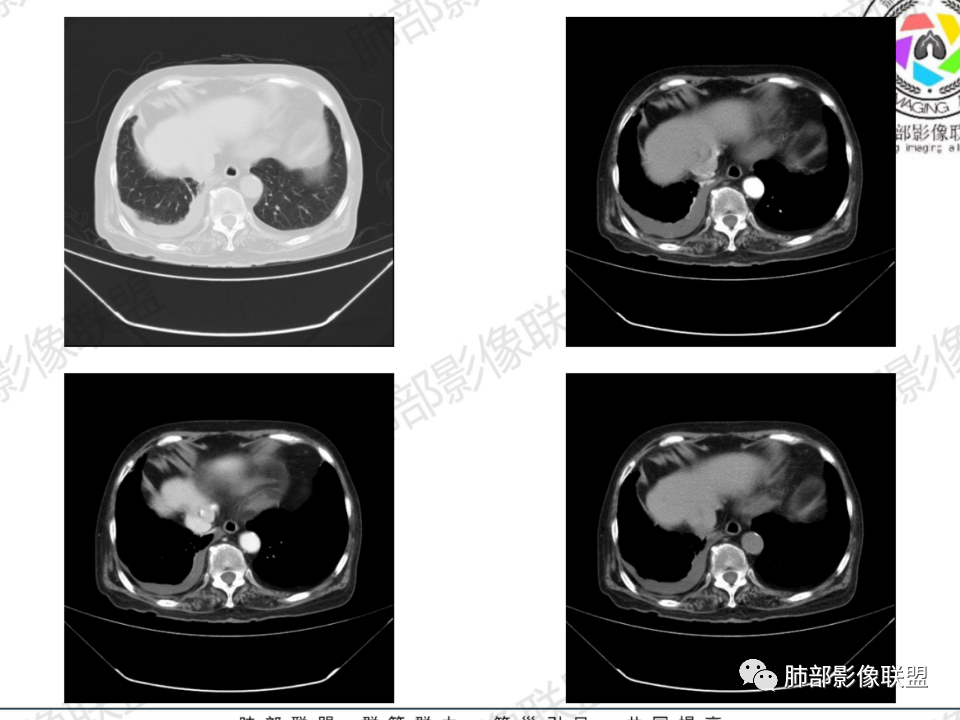

老年患者,病程中等,有咳嗽/喘息/低热症状,肿瘤标志物升高,感染标志物不高,右上肺新生物,中央型,边界清楚,有分叶,支气管截断,内有坏死,不均匀强化,考虑肺癌,鳞癌?

那个人:老年女性,亚急性病程,咳嗽发热。有垂体前叶功能减退,目前激素替代治疗,长期激素,量小,不知道累积量,没有目前激素水平指标。既往有淋巴结结核病史。肿瘤标记物Ca125升高。血沉升高,C反应蛋白轻度异常。影像,右肺上叶靠近肺门团块影,右肺门淋巴结钙化肿大,支气管狭窄,局部增厚,团块影外朝内改变,强化明显,血管破坏不明显,有粘液。和纵隔胸膜分界清楚,周围肺组织有斑片渗出影,右侧胸腔积液,考虑炎性?结核?支气管镜检查除外恶性飞鹰行动:老年患者,影像表现 右肺上叶占位性病变,边界清楚,有分叶征,内见细小钙化,右肺上叶支气管截断,增强病灶不均匀强化,病灶内有条状坏死区(扩张的支气管?),纵膈内未见增大淋巴结,考虑炎性病变,结核可能。一切∮随缘:右肺上叶实性肿块形态不规则,呈三角形,边缘分叶,边界伴有磨玻璃影,近段支气管未见明显显示,可能堵塞,病变平扫密度均匀,增强后可见低密度坏死无强化,周围略强化,右肺下叶散在结节。心包积液,及右侧胸腔积液,临床:有低热,低蛋白血症,肿瘤标记物高,考虑恶性:腺癌,神经内分泌癌(强化偏弱了),淋巴瘤,鉴别:结核红星:老年女性患者右肺上叶,肺门上区 分叶状肿块 ,右肺上叶支气管显示不清,增强扫描肿块,中等程度强化可见小斑片状坏死区,病灶内部可见斑点状钙化灶,病灶周围可见斑片状及小斑点状影,纵膈淋巴结增大,其他区域,胸膜下可见斑点状钙化。考虑肉芽肿性病变,结核的可能性大。老年患者最排除肿瘤性病变腺癌。土娃:右上肺不规则肿块影,边缘分叶,边界磨玻璃影欠清,病灶分叉状,内见点状钙化影及坏死灶,支气管堵塞,病灶增强强化不明显。考虑瘤样结核,鉴别淋巴瘤。张小兵:老年女性,亚急性病程,右肺上叶见不规则肿块,边缘平直凹陷为主,周围GGO边界不清,内见点状钙化及坏死灶,增强持续性渐进强化,右侧少量胸腔积液,双肺门及纵隔肿大淋巴结伴钙化,综合考虑慢性炎症。saf:老年患者,影像表现 右肺上叶占位性病变,边界清楚,有分叶征,增强病灶明显不均匀强化,纵膈内未见增大淋巴结,考虑炎性病变,结核可能。小兜:老年女性,咳嗽喘息一月,发热三天,肿瘤标志物升高,长期激素替代治疗。CT示右肺上叶近肺门不规则实变影,周围伴磨玻璃影,增强持续性渐进强化,内部血管破坏不厉害,内部可见多发条形低密度灶,右侧胸腔可见少量积液,双肺门及纵隔可见钙化淋巴结,考虑为炎性病变,结核可能玫:女,79咳嗽,喘息一月,发热三天入院,右肺上叶不规则形软组织密度肿块影,边界清晰,边缘见分叶及细短毛刺,病灶内见点状钙化影及稍低密度区,病灶边缘呈磨玻璃样改变,增强扫描,病灶呈不均匀性强化,考虑炎性病变,鉴别鳞癌。大雄:老年女性,既往诊断淋巴结结核,提示已治愈,近2年服用激素,诱导结核复燃→发热;纵隔肺门淋巴结肿大钙化,压迫支气管,右肺上中下叶支气管均狭窄→喘息咳嗽;尖段支气管受累闭塞→肺不张、支气管粘液栓;累及胸膜,结核性胸膜炎并胸水→右侧胸痛;实验室,血沉快,CA125高,低蛋白,符合;下一步,支气管镜尖段支气管刷检抗酸染色周太狼:老年女性,亚急性病程,肿瘤标志物升高。CT示右肺上叶尖段不规则肿块影,有分叶、收缩,周围伴磨玻璃影,增强渐进强化,内部可见多发条形低密度灶,右侧胸腔及心包少量积液,纵隔内淋巴结稍增大。倾向于恶性病变,肺癌伴阻塞性炎变可能。丽:老年女性,右肺上叶不规则软组织肿块,边缘清晰,内密度不均,可见点状钙化及粘液栓,周围可见片状高密度影,增强后均匀强化,内多发低密度,纵膈多发钙化淋巴结,考虑结核可能大,建议结合支气管镜检查除外肿瘤宇宙:右胸廓缩小,右肺上叶团块影及不张,平直边,周围磨玻璃影,纤细胸膜牵拉,上叶尖段支气管堵塞,明显延迟强化,可见支气管粘液栓,两肺门钙化淋巴结,右侧胸水,考性炎性肉芽肿,鉴别腺癌王秀仙:右肺上叶肺门区肿块,上叶支气管开口阻塞,形态不规则,密度不均,内可见支气管粘液栓及多发小灶性坏死,周围磨玻璃影边缘模糊,渐进强化,右侧胸腔积液、胸膜钙化,考虑炎性肉芽肿性病变,慢性炎症。鉴别鳞癌,结核。刘丹:老年女性,右肺上叶肿块伴钙化,右肺上叶支气管截断,增强后均匀强化,周边可见点片状模糊影,右侧胸腔积液,右肺门淋巴结增大,考虑占位并阻塞性炎症,肿瘤?结核?建议纤支镜检查。小飞:右肺上叶纵隔旁软组织肿块,边缘深分叶、长毛刺及毛刷样短毛刺,边缘磨玻璃影,磨玻璃边界模糊,支气管截断,平扫密度不均,可见点状钙化,增强不均匀明显强化,心影增大,心包积液,右侧胸腔积液,考虑恶性肿瘤,腺癌?秦化君:右肺上叶不规则分叶软组织密度肿块,边缘清晰,胸膜牵拉,周围花花草草,上叶尖段支气管阻塞,内可见点状钙化,增强后密度不均可见支气管粘液栓及坏死区,内见血管分枝。中间段及中叶,下叶支气管狭窄,壁见钙化。右肺门淋巴结肿大,右侧胸腔积液,心包粘连肥厚。考虑1右上肺恶性病变,鳞癌?2右肺多叶段支气管狭窄,考虑支气管内膜结核?3胸腔积液及肺门淋巴结肿大,转移?风儿:老年女性,右肺上叶肿块,形态不规则,外围大内带小,边缘分叶膨隆平直及毛糙,密度不均,内见支气管粘液栓及多发小灶性坏死,坏死边缘清晰 ,渐进强化,上叶尖段支气管阻塞,叶支气管壁有局限性增厚,邻近胸膜腔微积液;纵隔及双肺门淋巴结肿大,部分钙化,右侧胸腔积液、心包积液、胸膜钙化,考虑炎性,肉芽肿性结核可能性大。鉴别鳞癌,女性及血供均不支持;腺癌,坏死边界太清晰。流心明智:老年女性,79岁,咳嗽、气短1月,发热3天。胸CT:右肺上叶见不规则肿块,边缘有膨隆、有平直凹陷,周围GGO边界不清,病灶内见点状钙化、粘液栓,尖段支气管未见,增强持续性渐进强化,右侧少量胸腔积液,双肺门及纵隔肿大淋巴结伴钙化,肺动脉增粗。考虑:右上叶尖段堵塞并慢性炎症,支气管TB并结石?鉴别Ca

右肺体积小,提示既往结核

支气管影

前,后段都在,没有堵塞

支气管壁增厚,周围磨玻璃边界不清,提示炎症。胸膜下钙化符合结核

近期发热符合感染

这个层面往上应该是尖段,显示不清

背段支气管周围增厚伴钙化,符合结核改变

胸腔积液并胸膜钙化,符合结核;

结核是肯定有。现在最大问题是尖段

近端显示不清,但是远端是粘液栓,可以认为是还行的

如果是近端鳞癌,远端应该会堵塞,不会整个肿块里面还有较为通畅的支气管

这个区域我们看到密度与周围一致,并不是肺癌伴周围不张的感觉,所以鳞癌暂时是不支持的

临床信息:老年女性,亚急性病程,咳嗽发热。有激素使用史。既往有淋巴结结核病史。肿瘤标记物Ca125升高。血沉升高,C反应蛋白轻度异常。 影像所见:右侧胸廓相对狭小,右肺上叶不规则团块影贴附纵隔旁,轻度分叶,整体密度较均匀,偶见钙点。

相应上叶尖端及前段支气管开口未能追踪(阻塞),开口处见钙化。病灶渐进性强化,并衬托出较完整尖段及前段含液支气管影。支气管开口区域未见异常高密度强化(如类癌等)及相对乏血供区(如鳞癌)。病灶区未见液化坏死。右上纵隔及胸廓入口区未见病灶胸膜外突破(栽赃)。

右肺上叶后段等区域散在片状影,边界不清(提示渗出性病灶)。

纵隔及双肺门见钙化淋巴结。心包积液,右侧胸腔积液(提示存在活动新病灶)。双侧胸膜下见多发斑点状钙化,胸廓变形(提示存在结核基础病变可能)。 诊断意见:综上,右肺上叶块状影更符合继发性肺结核。 最后小结:既往诊断淋巴结结核,提示已治愈。近2年服用激素,可疑诱导结核复燃,也可引起发热。纵隔肺门淋巴结肿大钙化,压迫支气管,右肺上中下叶支气管均狭窄,所以引起喘息咳嗽。尖段支气管受累闭塞,导致肺不张、支气管粘液栓,出现条状无强化区。病变累及胸膜,导致结核性胸膜炎并胸水,引起右侧胸痛。实验室检查血沉快,CA125高,低蛋白,均符合结核。下一步,建议支气管镜尖段支气管刷检并抗酸染色。(本段摘自於雄老师精彩发言)